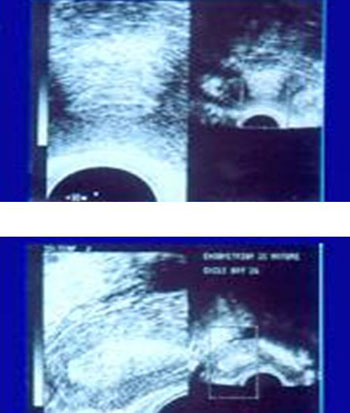

Εικόνα 4. Προωθυλακιορρηκτικό

ώριμο ενδομήτριο πρόσφορο για εμφύτευση. Η τριζωνική του δομή είναι ευκρινής,

ενώ το παρέγχυμα εμφανίζει μετρίου βαθμού ηχοϊκότητα ενδεικτική παρουσίας εκκρίματος,

που ήδη πληρεί τους αδένες. Η διάμετρος υπερβαίνει τα 7 χιλ.

Εικόνα 5. Επάνω: ώριμο προωοθυλακιορρηκτικό

ενδομήτριο.

Κάτω: υπερώριμο ενδομήτριο ασυμβίβαστο με εμφύτευση. Η τριζωνική του δομή έχει

απολεσθεί, ολόκληρο δε το παρέγχυμα εμφανίζεται έντονα υπερηχοϊκό.